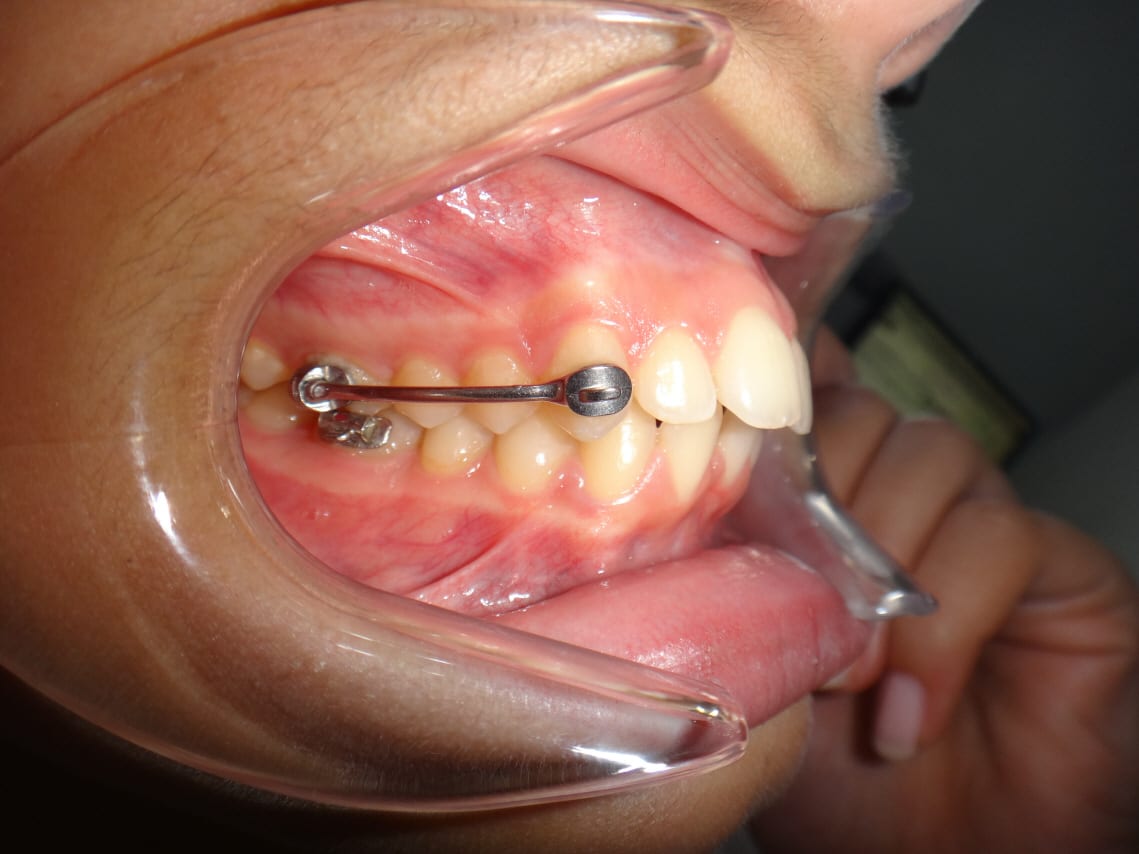

Une variante de carriére est de faire du segmental avec des bracket ( HSD ) . Si join un patient vue aujourd'huit avec un peut plus de trois mois de HSD

Un cas avec HSD en lingual :-) encore